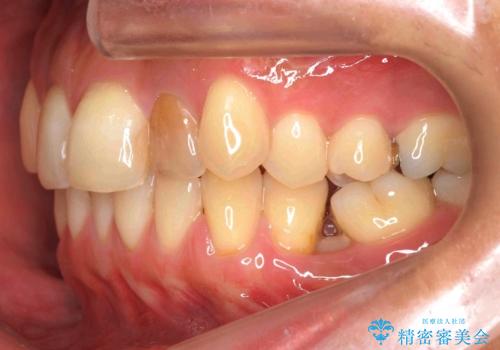

埋まっている奥歯を並べることで、その後ろの倒れ込んだ歯を整直させることができました。

上の歯はマウスピース矯正で、奥歯を後ろに下げて、左のかみ合わせのズレを直しています。

上下とも非抜歯で並べています。